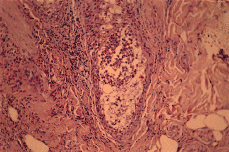

Realizadas dos biopsias cutáneas ambas revelaron hallazgos semejantes (Fig. 4). Se trataba de un proceso inflamatorio centrado en el folículo piloso, cuyo canal infundibular aparecía ocupado por un absceso que, secundariamente, daba lugar a imágenes de vesículas epidérmicas subcórneas en la vecindad del óstium folicular. La infiltración inflamatoria era causa de exocitosis en la pared del infundíbulo folicular y en la glándula sebácea. Entre las células inflamatorias destacaba un gran número de eosinófilos. Existía, además, un infiltrado inflamatorio muy rico en eosinófilos, de localización perivascular y perifolicular. Realizada tinción con azul alcián a pH 2,5, se puso de manifiesto la presencia de mucina, en cantidad algo mayor de la habitual, en el interior de algunas estructuras foliculares, entre las células del infiltrado inflamatorio (Fig. 5).

FIG. 4.--Absceso folicular con gran número de eosinófilos.